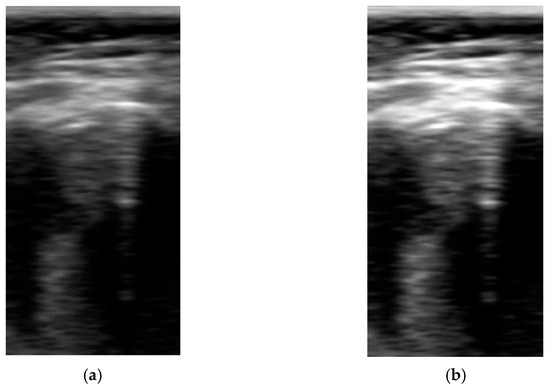

Pre-Processing Block